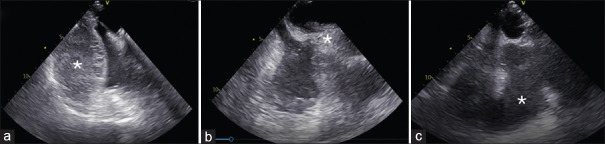

Abstract: Although most superior vena cava (SVC) syndromes are due to intrathoracic malignancies, some are iatrogenic, such as those following the intravenous implantation of pacemaker wires. To date, the occurrence of this syndrome after epicardial pacemaker removal has not been described. The initial auricular laceration after removal can be complicated by the administration of anticoagulant and antiplatelet drugs, forming a hematoma that compresses the SVC cranially. Therefore, standardized practice may be necessary in these patients to address anticoagulant and antiplatelet therapy, perform serial echocardiography, and pay attention to underlying symptoms, which may be insidious and delayed.